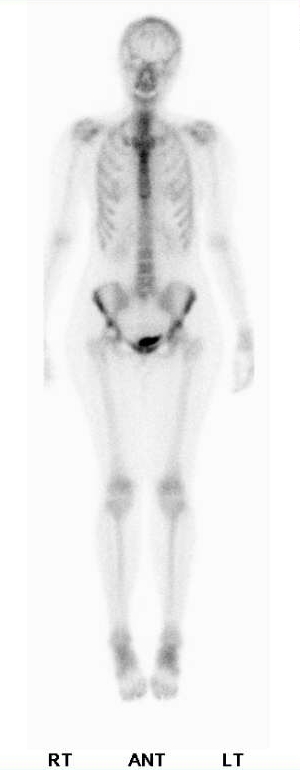

★到底是不是假影?

這是一位30多歲的肺癌女性患者,在連續的bone scan追蹤系列影像,由於是肺癌患者,所以大家的焦點都集中在肺部,可是在中間的那一次檢查裡,我們的醫生突然發現病人右邊的股骨頸那邊好像出現了甜甜圈的影像,該不會是治療的藥物造成了那邊的缺血性壞死AVN?於是就在報告上提到了這件事,然後臨床的醫師也很關心這個情形,就安排了核磁共振,結果卻是正常,接著病人又來進行第3次的bone scan追蹤,這次原先懷疑是AVN的地方竟然就沒事了,我跟我們家的醫師反反覆覆的看了幾次影像的原始檔,最後得出的結論是,第2次的影像有可能是口袋裡有銅板,造成的影像缺損才會那麼的圓,但是由於當時也沒有補局部的影像,因此一切也都是猜測。這件事告訴我們,首先,就算是已經確定病情的患者,在判讀影像時也要多留意其他的區域,才不至於有遺漏的地方,再者,就算病人說身上都沒有金屬或是其他異物,也不代表你可以放心的照,看到怪怪的地方,還是多檢查一遍會比較好。

2018/7/23 |

2018/10/19 |

2019/1/14 |